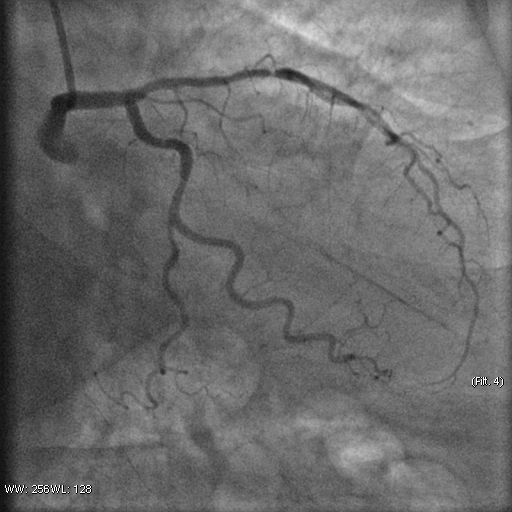

Stenosis of the anterior interventricular artery in the 6.7 segment is 95%. Stenosis of the orifice of the diagonal artery of the 1st order is 95%. Stenosis of the circumflex artery in the 13th segment is 40%. During coronary angiography, pronounced spasm is noted in the 2nd segment of the right coronary artery with complete occlusion of the artery lumen. After stopping the spasm, coronary angiography shows a spiral (spontaneous) dissection of the right coronary artery from segments 1 to 3.

A guiding catheter JR 3.5 6Fr was inserted along a 0.035" 260.0 cm guidewire. The guidewire was removed. The right coronary artery was catheterized. A 7Fr Y-click connector (complete with an insertion device and a guidewire rotation device) was connected to the guiding catheter. A coronary guidewire Whisper ES 0.014" 190 cm, Asahi Gaia Third 0.014" 190 cm was inserted and brought into the orifice of the right coronary artery. The guidewire was inserted beyond the lesion zone of the right coronary artery in segment 2, then into the distal sections. Wilma NC 2.00*20.0 mm and Wilma NC 3.00*15.0 mm balloon catheters were inserted alternately along the coronary guidewire - predilation of the lesion zone of the right coronary artery in segment 2 was performed. Inflation of balloon catheters 14 atm. with an inflator, the balloon catheters are deflated and removed. A stent is inserted along the coronary guidewire - the Yukon Chrom PC 3.0 * 28.0 mm system, Yukon Chrom PC 3.0 * 28.0 mm, Cid Cre 8 3.50 * 25.0 mm, Cid Cre 8 4.0 * 16.0 mm - the stent is implanted in the lesion area of the right coronary artery in the 2nd segment. Inflation of the balloon catheter 9-16 atm. with an inflator, the balloon catheter is deflated and removed. Control coronary angiography - blood flow in the stenting zone is TIMI3, there are no signs of dissection or stent dislocation.